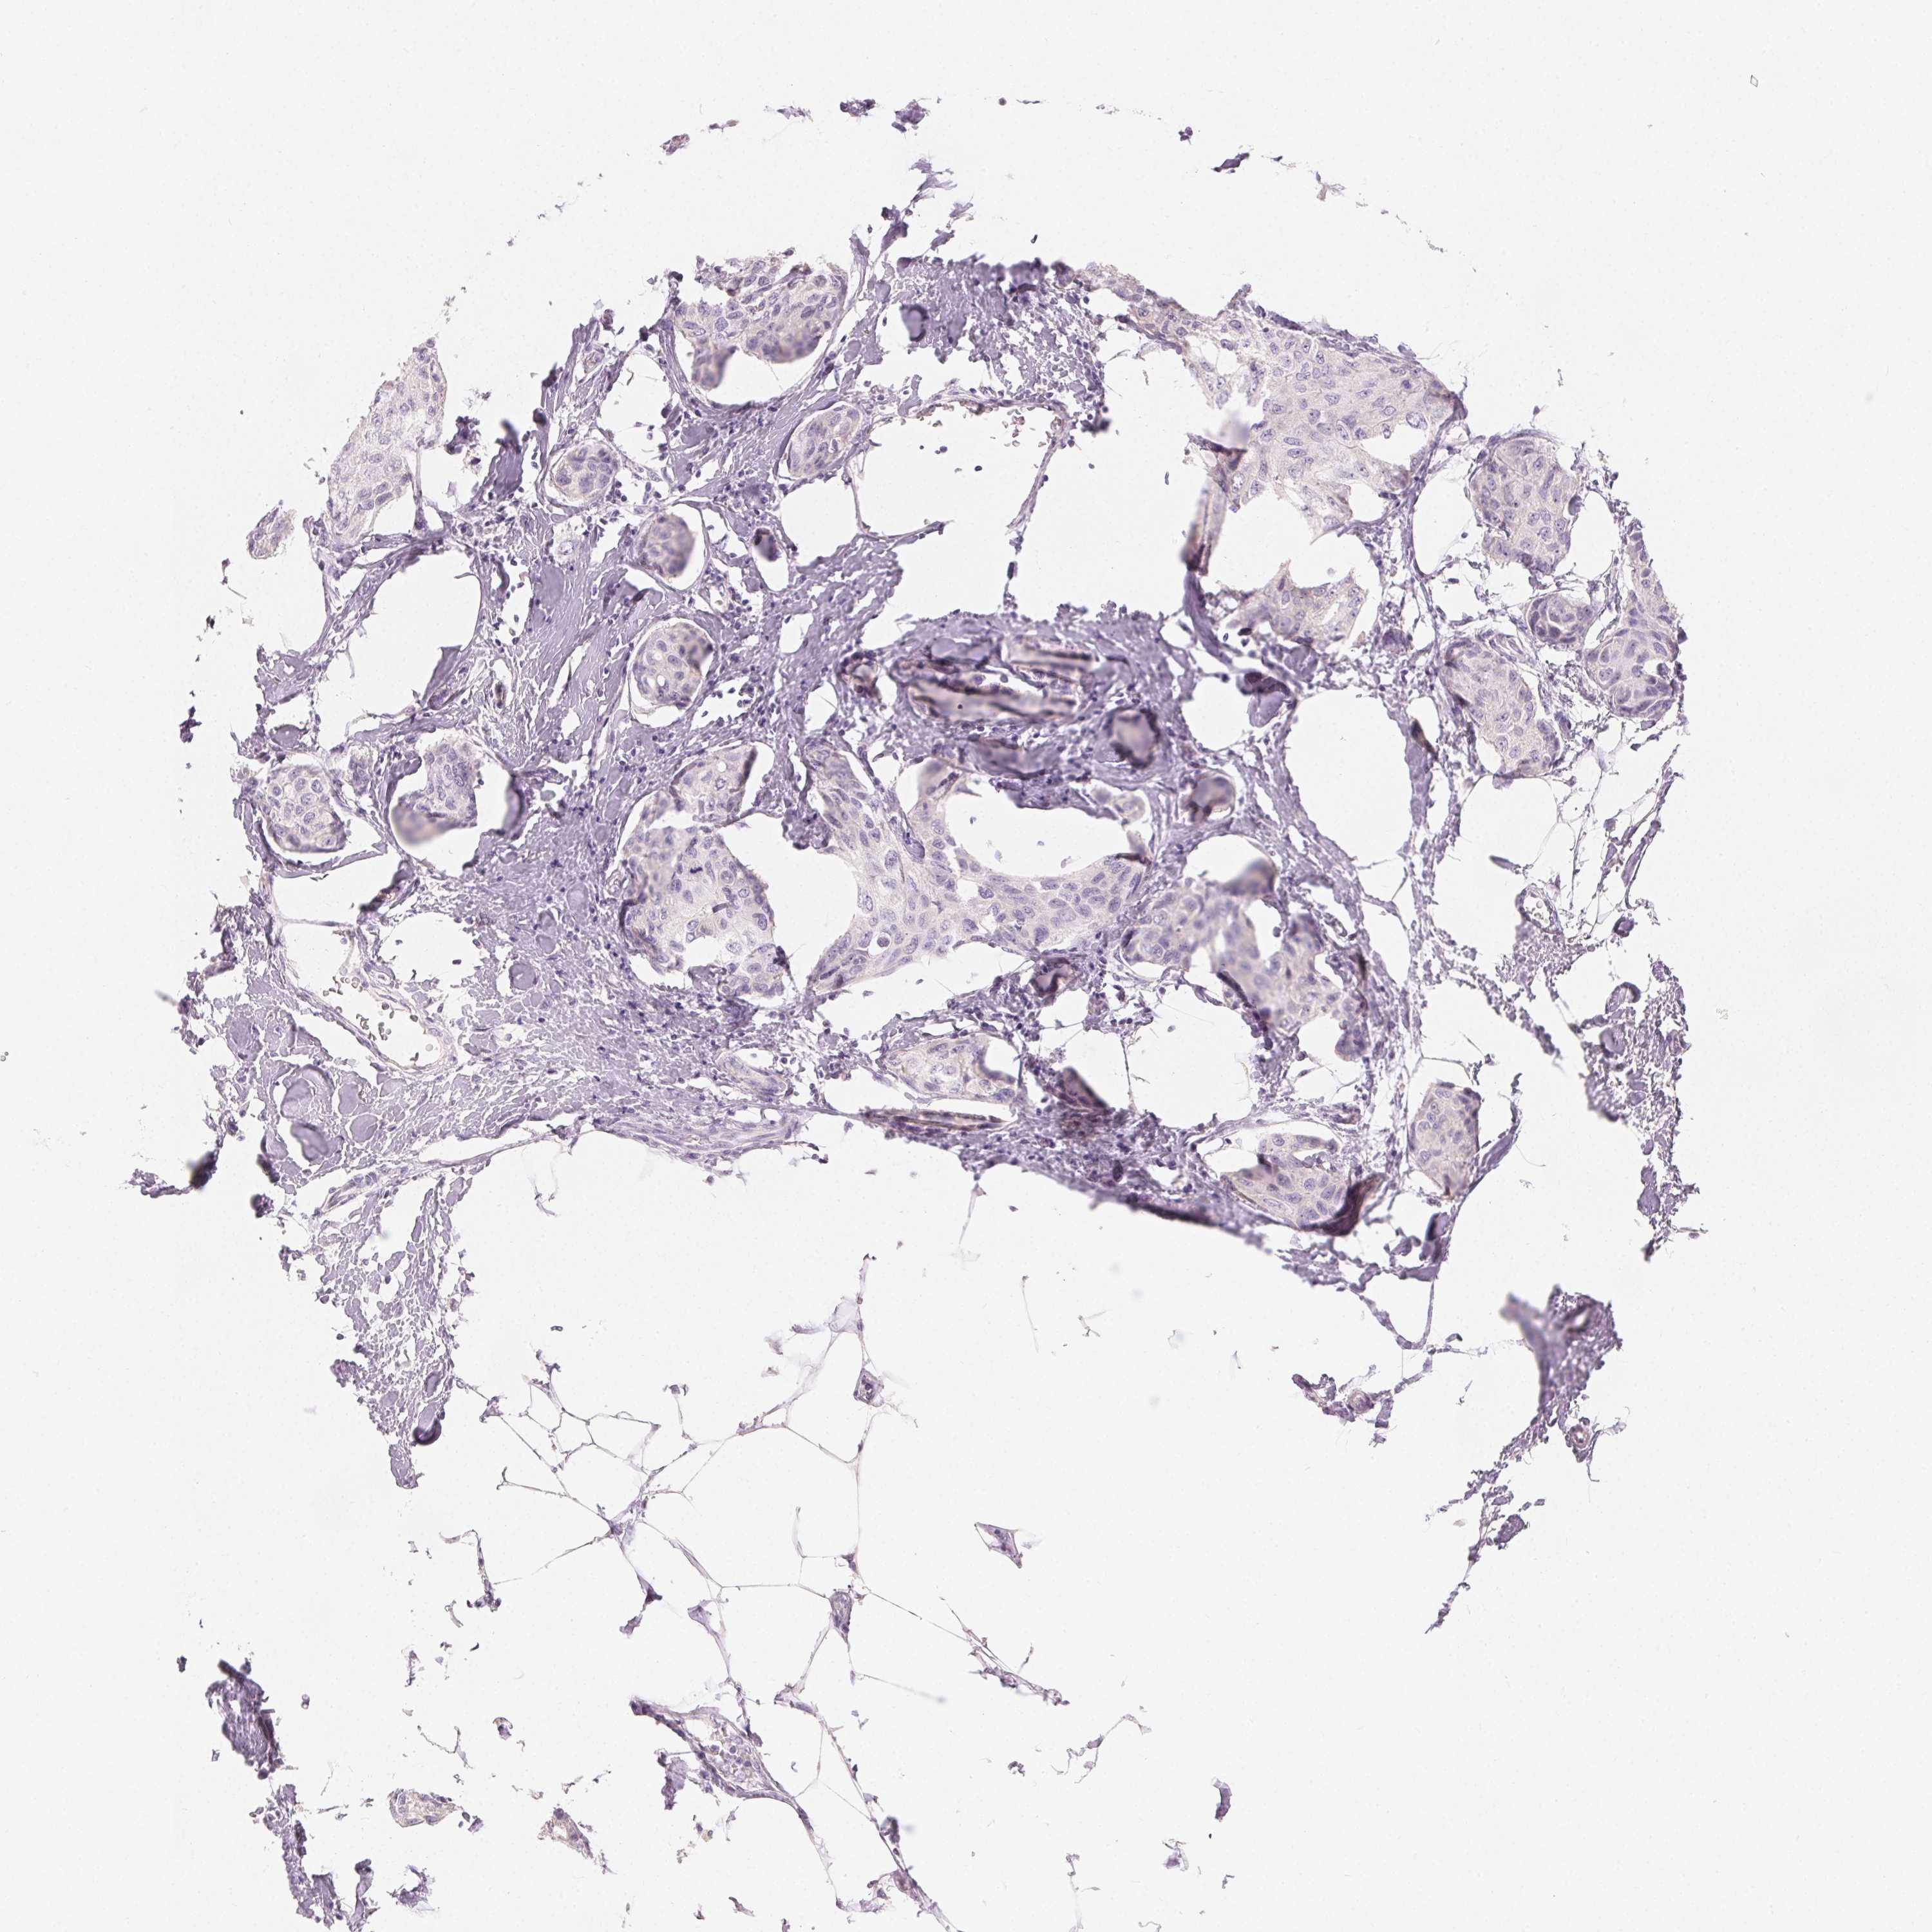

CANCER BREAST CANCER Show tissue menu

Breast cancer

Human cancer